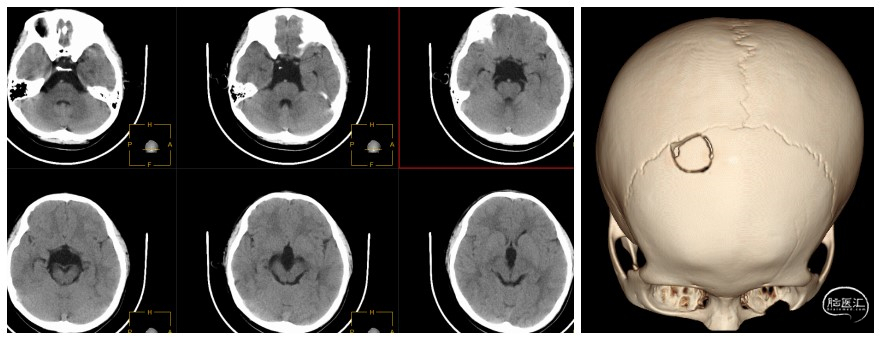

患儿 男 8岁,因“颅脑外伤查体发现鞍上池蛛网膜囊肿合并脑积水”入院。

神志清,精神好,无特殊不适症状。查体未发现阳性体征。

患儿鞍上池蛛网膜囊肿合并脑积水,诊断成立。完善术前检查,行神经导航下脑室镜鞍上池囊肿双造瘘术。